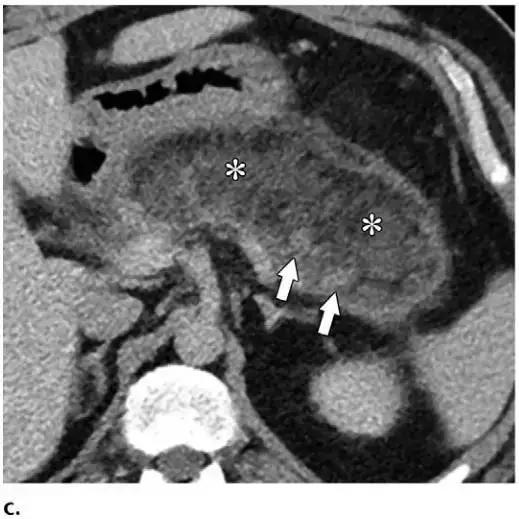

同时受累的亚型:表现为胰腺及胰周无强化坏死物,多累及小网膜囊和肾前间隙(图 3a)。

胰周型:表现为胰腺强化正常,而胰周坏死,坏死物可包括不等量的液体和和非液性成分,约占坏死性胰腺炎的 20%(图 3b)。

图 3 坏死性胰腺炎亚型在增强轴位 CT 的表现。a 胰腺和胰周同时受累的 58 岁女性患者,胰体无强化(*),正常强化的胰尾(黑箭头),小网膜囊内 ANC(白箭头)。b 仅胰周受累的 18 岁男性患者,可见一周为大片不均质密度(箭头),和 ANC 相符。胰腺实质密度正常(*)。c 仅胰腺实质受累的 33 岁男性患者,可见大片局限无强化的胰腺实质和脂肪密度(*),诊断为 WON。仅周边可见少量残余强化的胰腺实质(箭头)